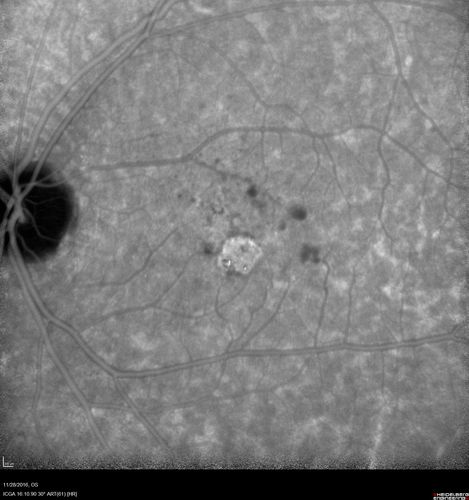

Confluent Soft Drusen with Subetinal Fluid - Right Eye

Asymptomatic 85 year old man.  OCT shows pocket of subfoveal fluid in the center of the macula.  This could be mechanical from the drusen preventing the retina from settling down.  Testing did not reveal a CNVM and subsequent OCT 6 weeks later showed no change in structure.